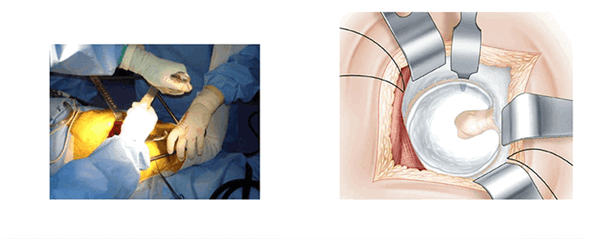

Модифицированный боковой доступ к тазобедренному суставу включает следующие этапы: разрез кожи в проекции большого вертела, рассечение широкой фасции бедра, выполнение трёх разрезов. Первый разрез от проксимальной точки по ходу мышечных волокон средней ягодичной мышцы в передне-верхнем направлении длиной 3 см, второй разрез от точки на границе между средней и дистальной третью большого вертела в направлении кпереди, отступив от центральной линии 1 см, длиной 3 см, третий разрез производят, соединяя начальные точки первого и второго разрезов между собой в виде дуги, направленной выпуклой стороной кпереди (рисунок), отсекают среднюю ягодичную мышцу от передней поверхности большого вертела в пределах выполненных разрезов, полученный лоскут средней ягодичной мышцы смещают кпереди и фиксируют при помощи инструментов. Затем вывихивают головку бедренной кости и выполняют эндопротезирование тазобедренного сустава. После основного этапа смещённый кпереди сформированный мышечно-сухожильный лоскут укладывают на своё место и фиксируют при помощи швов [4].

Схема выполнения модифицированного бокового доступа к тазобедренному суставу пациентки Л.: на средней ягодичной мышце намечены три разреза для формирования лоскута (интраоперационное фото)